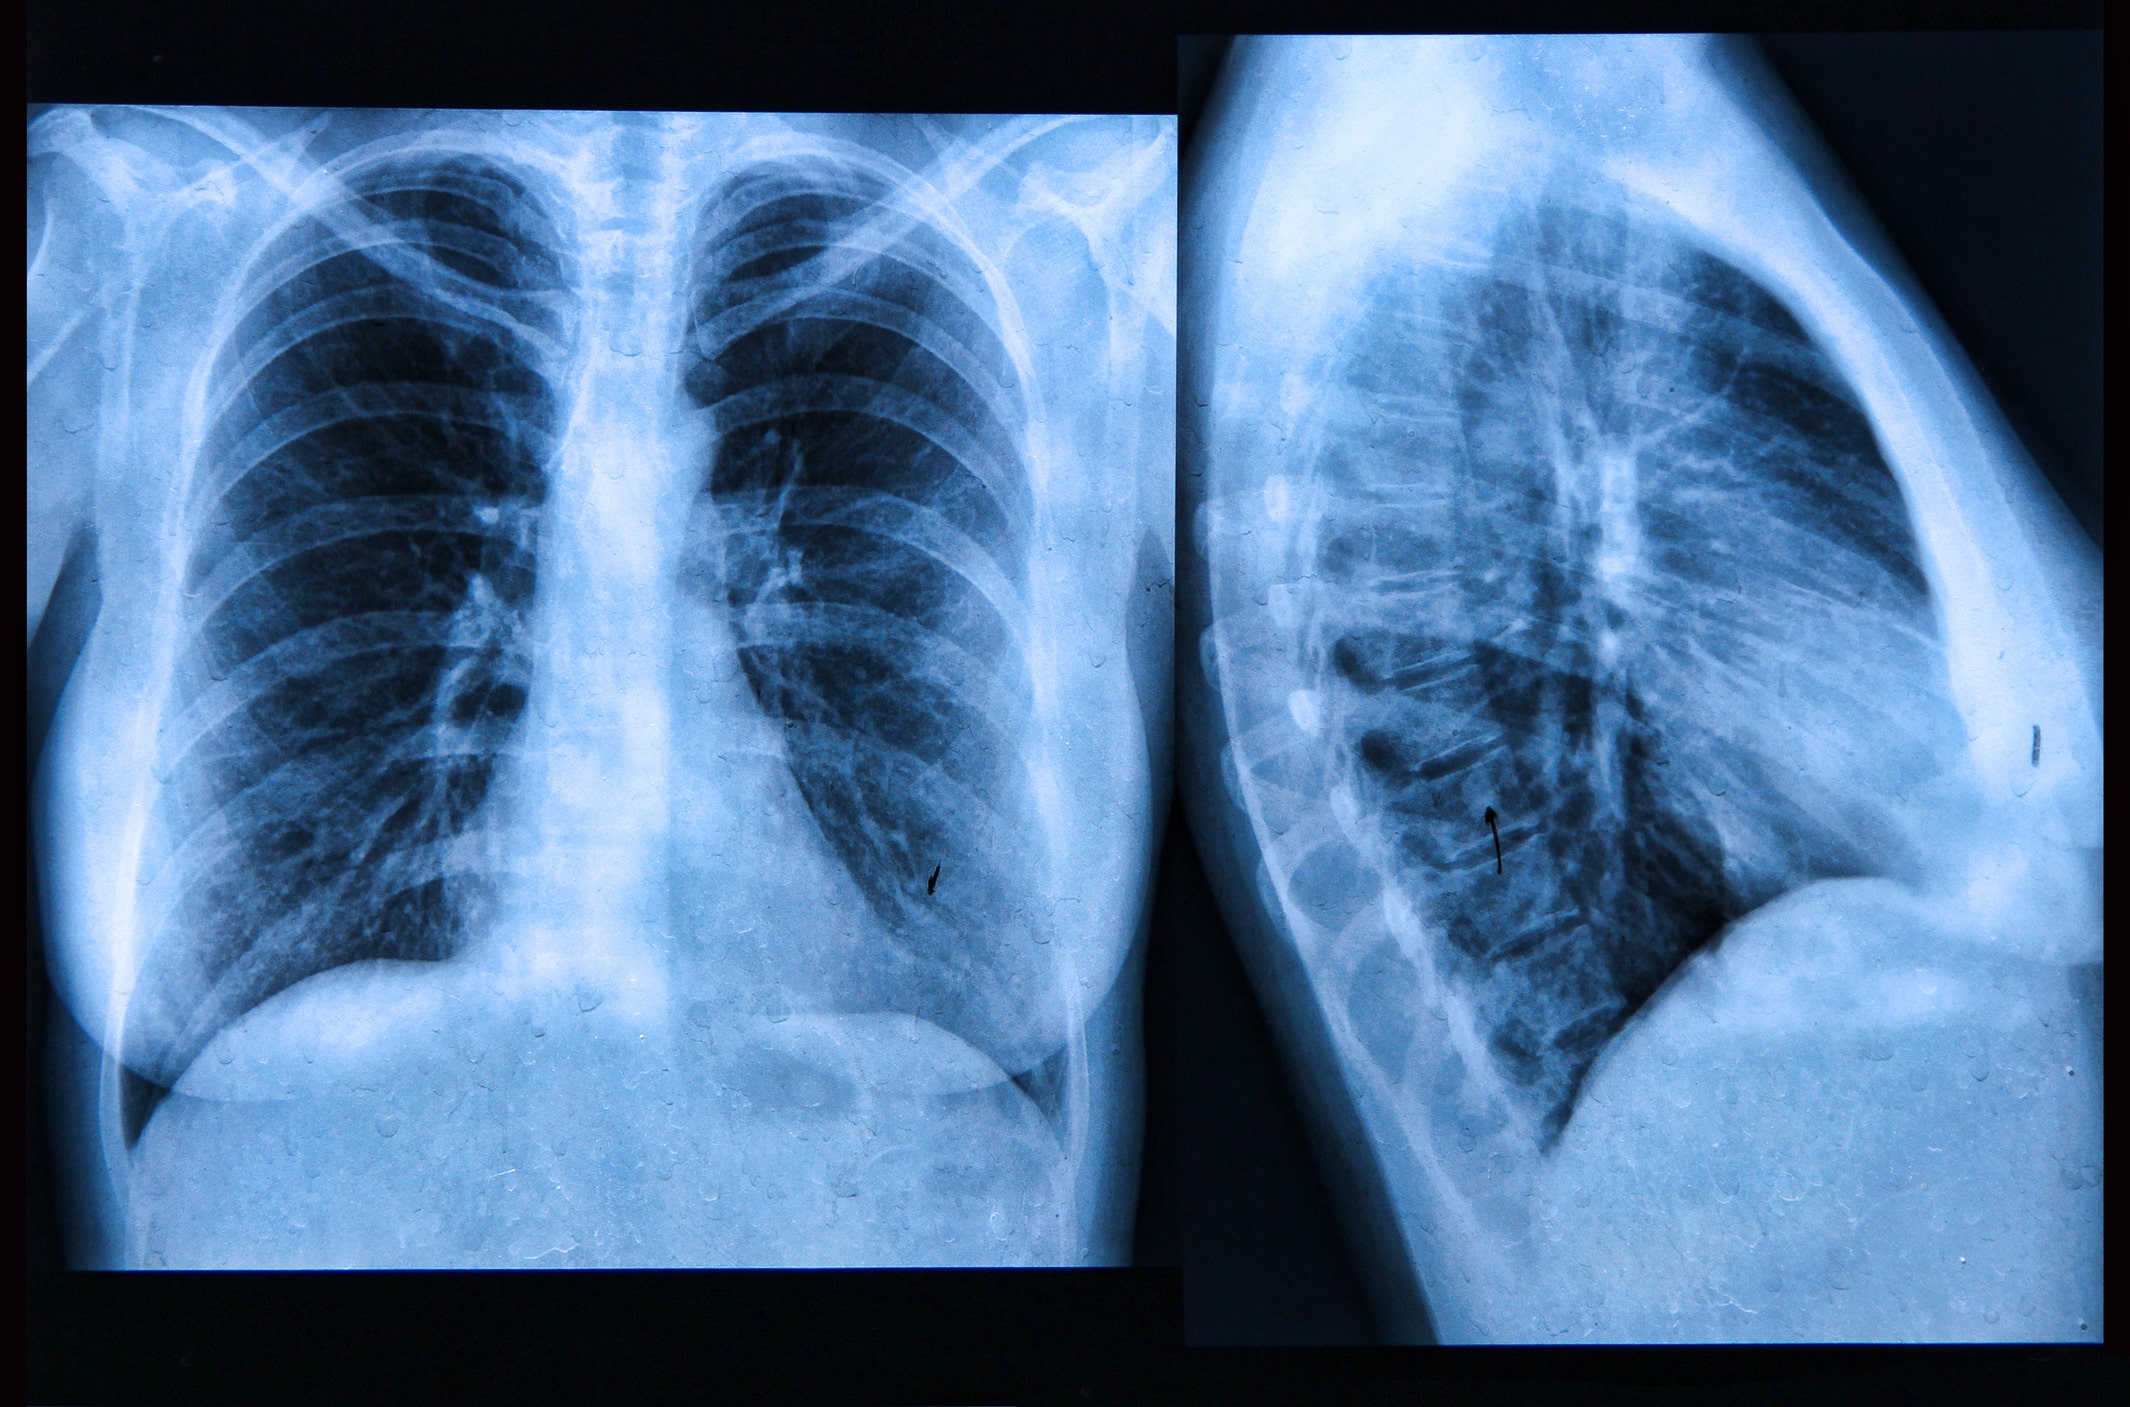

Рентген здоровых легких: примеры снимков и советы

Раздел: Сокровищница опыта